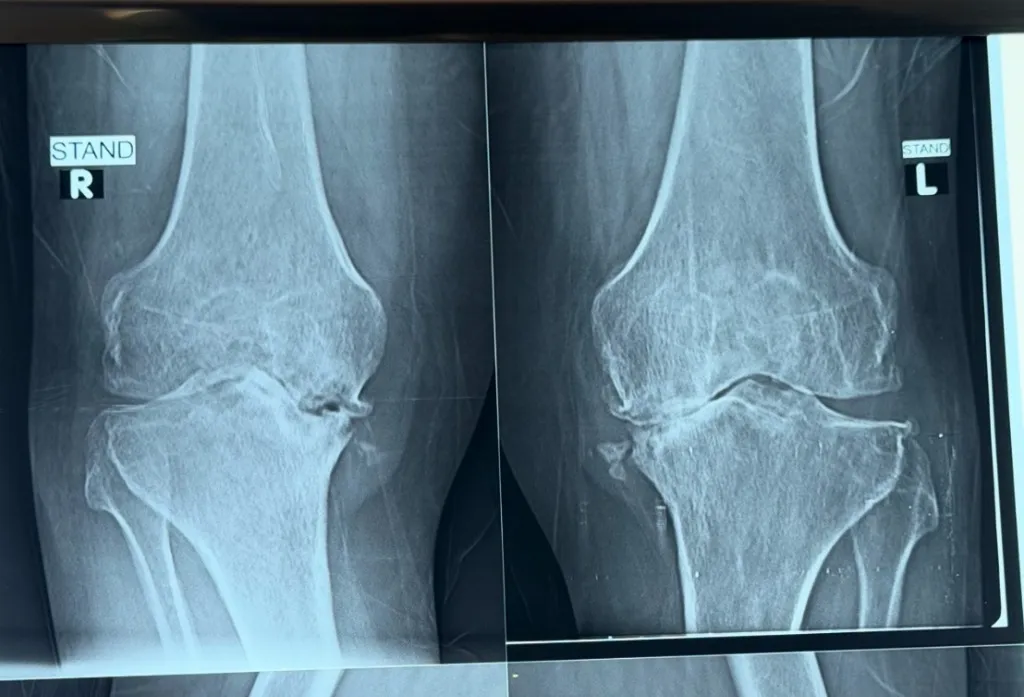

Grading Knee Arthritis

Grade 1

Minor bone spurs, minor symptoms. Conservative management is effective.

Grade 2

Visible joint space narrowing. PRP and physiotherapy can help significantly.

Grade 3

Significant cartilage loss. May benefit from viscosupplementation or arthroscopy.

Grade 4

Bone-on-bone contact. Knee replacement is often the definitive solution.